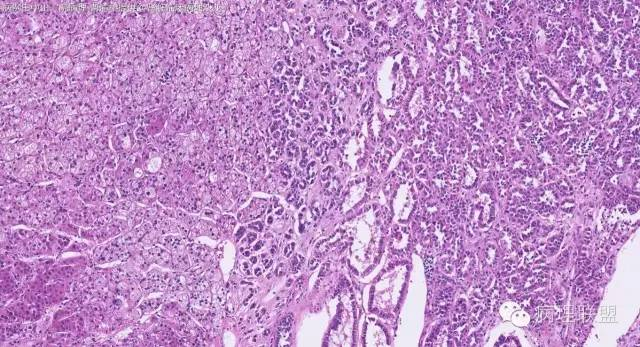

女性,50岁,肾上腺肿物(影像及手术均确认肿物位于肾上腺,界限清楚)。血压升高。(病例由 中山一院病理 曹清华提供,致谢!)

伴假腺样结构的肾上腺皮质腺瘤,合并髓脂肪瘤

从肿瘤的位置及镜下与肾上腺皮质的关系看,应该像是皮质来源肿瘤。假腺样结构的皮质腺瘤没有见过,似乎文献也还没查到。另外inhibina, melanA, syn均阴性(肿瘤旁正常皮质阳)感觉有点迷惑。。。请老师指教,有相关文献么?@武警嘉兴医院 周泉

假腺样是细胞粘附性差了导致。往往可以伴随黏液成分,组化上这几个抗体应该至少会有灶性阳性。

这个我再仔细看下。但,我们这例腺管结构不像是粘附差所致,是真的腺管;间质目前还没有看到有间质粘液变性区域;inhibina, syn, menlana是真的不阳,灶性都没有...